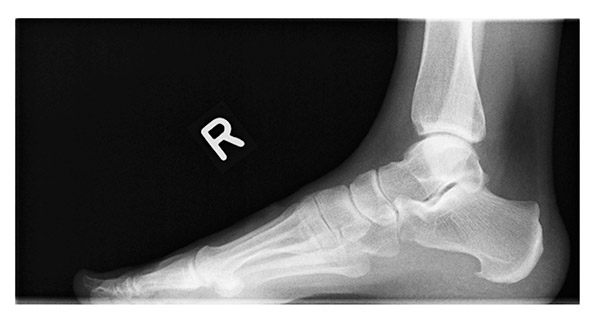

Abb. 1: Deutlich sichtbarer Knochensporn am Fersenbein (Calcaneus)

Begleitend kommt immer als verantwortlicher Auslöser die Schmerzhaftigkeit im Ansatzbereich der flächenhaften Fußsohlensehne sowie der kleinen Fußmuskeln als Sehnenentzündung hinzu. In etwa 50 % der Fälle eines solchen, auch röntgenologisch in der strengen Seitaufnahme des Fersenbeines gut zu sehenden Spornes (Abb. 1), kommt es zu Beschwerden. In der Regel werden diese von den Betroffenen als unangenehm empfunden, weil sie bei jedem Schritt verspürt werden. In Folge der dauernden Belastung wird auch der unter dem Fersenbein gelegene Schleimbeutel (Bursa subcalcanearis) gereizt, so dass nach zwei bis drei Monaten dauernder Schmerzsymptomatik bereits Ruheschmerz geklagt wird.

Die Beschwerdesymptomatik kann mit der Sporngröße korrelieren. Aber nicht immer lässt sich ein direkter Rückschluss zwischen Schmerz- und Röntgenbild herleiten. Die fast immer spitz zulaufende und in der Röntgendokumentation dornartig imponierende knöcherne Ausziehung kann zwischen zwei Millimetern und über deutlich einen Zentimeter groß sein.